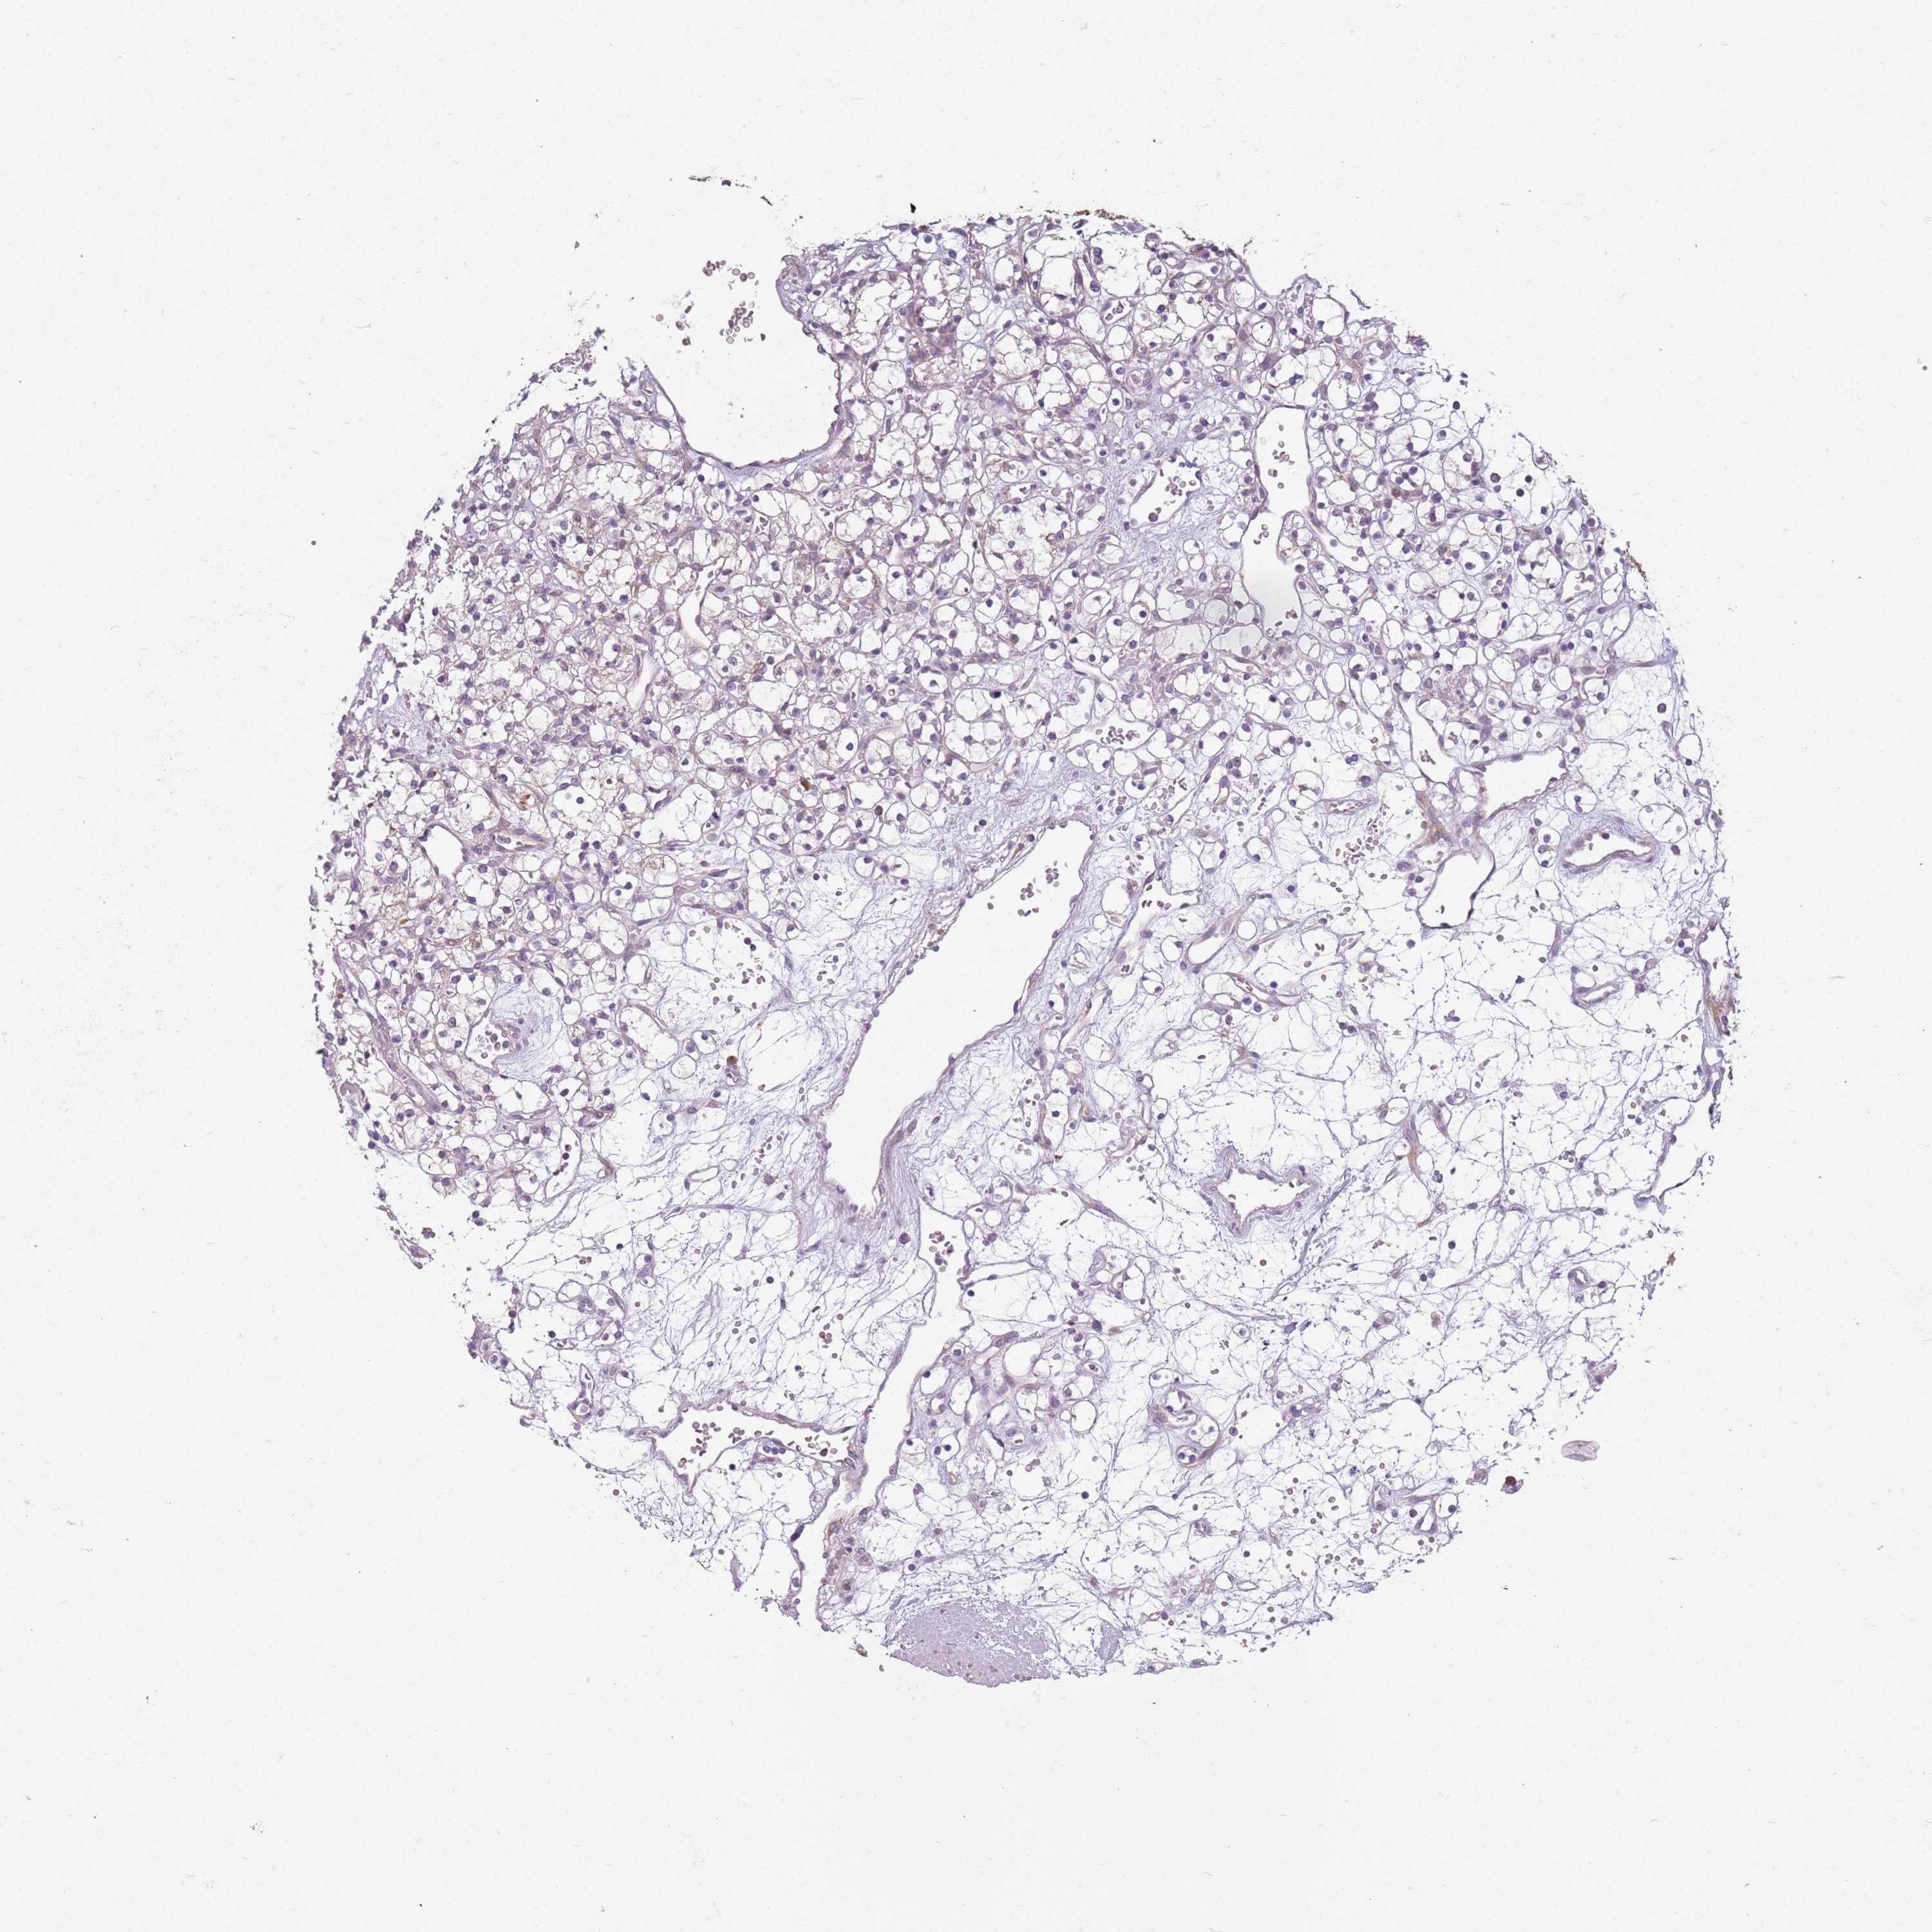

KIDNEY RENAL CLEAR CELL CARCINOMA (VALIDATION) - Interactive survival scatter ploti

The Survival Scatter plot shows the clinical status (i.e. dead or alive) for all individuals in the patient cohort, based on the same data that underlies the corresponding Kaplan-Meier plots. Patients that are alive at last time for follow-up are shown in blue and patients who have died during the study are shown in red.

The x-axis shows the expression levels (FPKM) of the investigated gene in the tumor tissue at the time of diagnosis. The y-axis shows the follow-up time after diagnosis (years). Both axes are complimented with kernel density curves demonstrating the data density over the axes. The top density plot shows the expression levels (FPKM) distribution among dead (red) and alive patients (blue). The right density plot shows the data density of the survived years of dead patients with high and low expression levels respectively, stratified using the cutoff indicated by the vertical dashed line through the Survival Scatter plot. This cutoff is automatically defined based on the FPKM cutoff that minimizes the p-score. The cutoff can be changed by dragging the vertical line or by entering a cutoff value in the square labeled "Current cut-off".

Under the Survival Scatter plot the p-score landscape (black curve; left axis) is shown together with dead median separation (red curve; right axis). Dead median separation is the difference in median mRNA expression between patients who have died with high and low expression, respectively. It is calculated as follows: median FPKM expression of dead patients with high expression - median FPKM expression of dead patients with low expression. This is intended to aid the user in visually exploring custom cutoffs and the associated p-scores and dead median separation.

Individual patient data is displayed and can be filtered by clicking on one or more of the category buttons on the top of the page. Categories describing expression level and patient information include: high, low, alive, dead, female, male and tumor stages. The scale of the x-axis can be toggled between linear and log-scale by clicking on the "x log" button. Mouse-over function shows TCGA ID, patient information and mRNA expression (FPKM) for each patient.

& Survival analysisi

Kaplan-Meier plots summarize results from analysis of correlation between mRNA expression level and patient survival. Patients were divided based on level of expression into one of the two groups "low" (under cut off) or "high" (over cut off). X-axis shows time for survival (years) and y-axis shows the probability of survival, where 1.0 corresponds to 100 percent.

RPS28 is not prognostic in Kidney Renal Clear Cell Carcinoma (validation)

: 205.86

Average pTPM 168.7

Number of samples 100